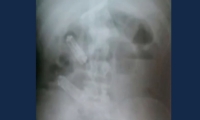

En la imagen de este rayos X se observan los celulares en el estómago del recluso.

Murió hombre tras pasar una semana con tres celulares en el estómago

No logró expulsarlos y murió antes de la cirugía. El caso ocurrió en Brasil.